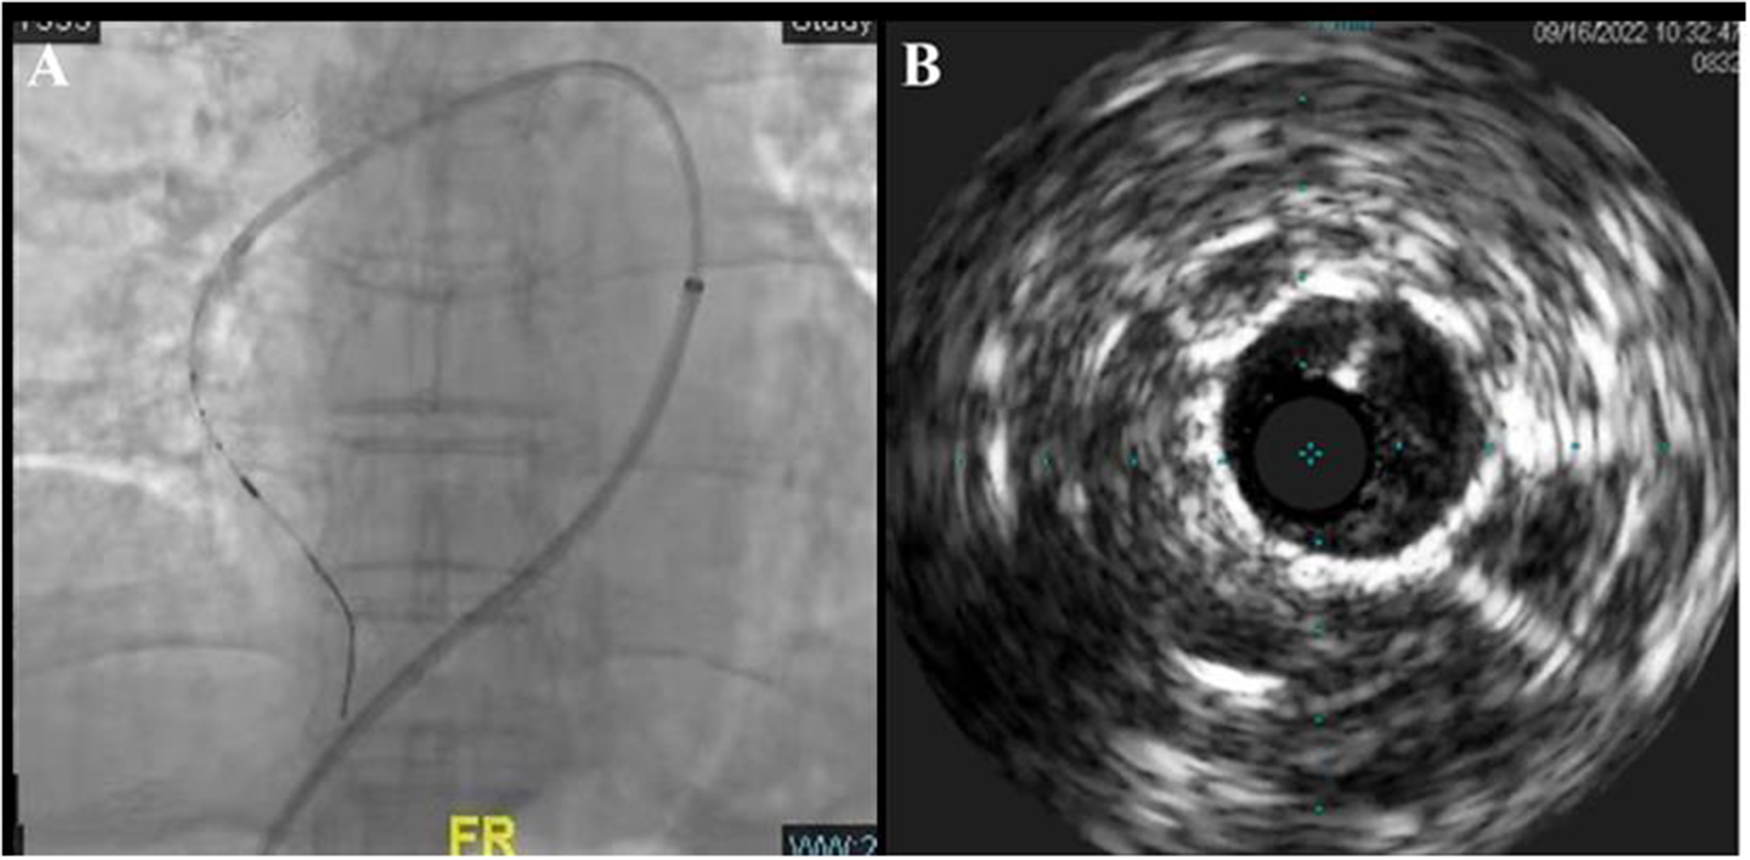

The pressure guide wires were placed into RA3, RA7, RA9, and RA10b, respectively, under real-time fusion of x-ray fluoroscopy and CTA 3D reconstruction images. The severity of a lesion in the pulmonary artery was evaluated by difference in pressure gradient between the proximal and distal sides of the lesion. The Pd/Pp ratio (the ratio of mean distal to mean proximal pressures) of all the above-mentioned blood vessels was greater than 0.7. At the entry of the pressure guidewire (Certus™, Abbott Medical) into the lateral branch of the right basal pulmonary artery (RA8a), the Pd/Pp ratio in the middle part of RA8a was the lowest at 0.48. Intravascular ultrasound (IVUS) was performed for the middle part of RA8a through angiographic navigation (Figure 2), and the diameter and length of the stenosis were measured. The balloon (Sprinter 3.0 × 15 mm) was selected according to the lumen diameter and placed into the stenosis of the middle RA8a, and segmental dilatation plasty (6–16 atm) was performed. After the plasty, the Pd/Pp ratio of the middle RA8a was 0.78, as measured by the pressure guide wire. Immediately after percutaneous procedure, which showed mPAP of 24 mmHg, mPAWP of 7 mmHg, CO of 5.4 L/min and PVR of 2.98 Wood units.

Figure 2

Real-time image fusion navigation technique and IVUS-guided BPA (A) and its intraluminal structure (B).